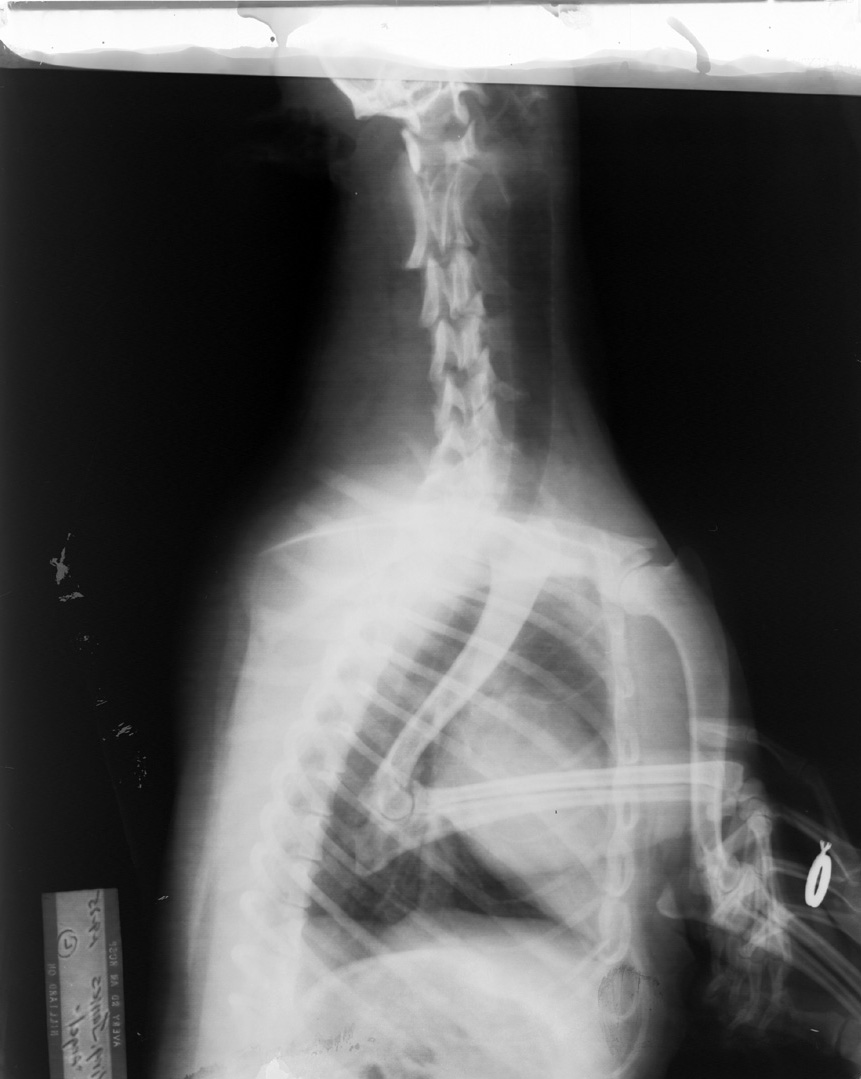

Fixer Left on Film, Manual Processing

Inadequate rinsing with brown discoloration due to fixer left on film, hand developed. Fluid levels in tanks too low; very top edge of the film was neither developed nor fixed: therefore, it still has emulsion on it. Clear area was fixed but not developed so all silver was removed from it. This rest of the film was developed and fixed. Note ungloved hand holding front leg. UNACCEPTABLE!!!!